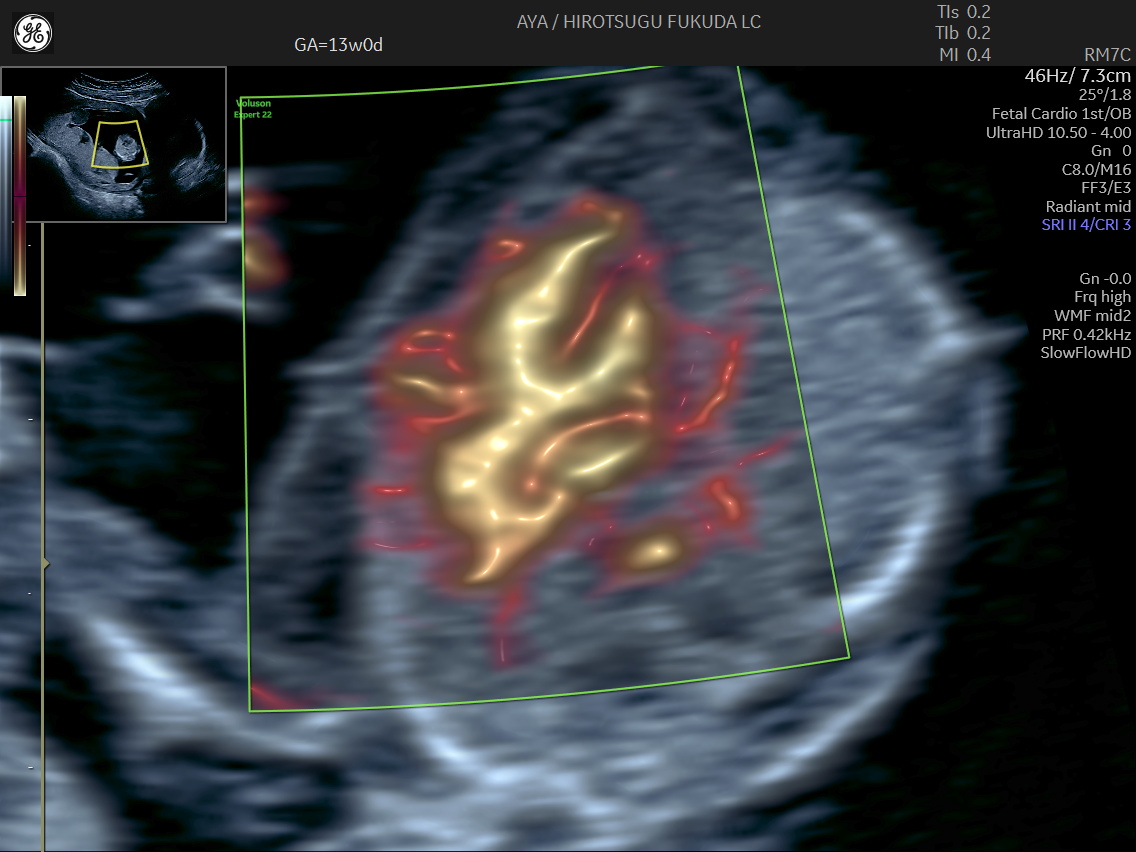

胎児心臓の初期評価

下記は、妊娠初期における血流描出の一例です。初期心臓評価に関する取り組みについては、国際学術誌 Journal of Ultrasound in Medicine にも報告しています。

First-Trimester Detection of Conotruncal Anomalies Using Transabdominal SlowflowHD: A Case Series and Proof-of-Concept Study

Hirotsugu Fukuda, Aya Fukuda, Kazuya Mimura, Masayuki Endo, Ritsuko K Pooh, Michiko Kodama

J Ultrasound Med. 2026 Jan;45(1):201-207. Epub 2025 Aug 19.

PMID: 40827753 DOI: 10.1002/jum.70037

妊娠13週のslowflowHDによる心臓

妊娠13週の心疾患症例